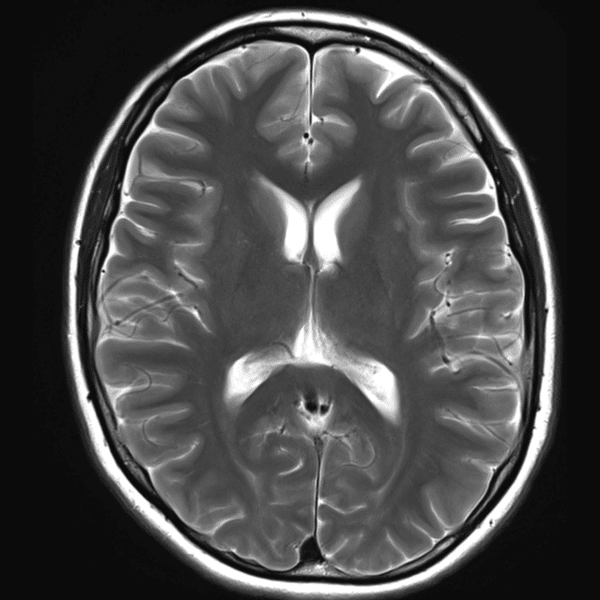

Brain T2WI

3.0T Siemens MAGNETOM Skyra

2D TSE

(L) 0.4×0.4×5.0 mm

(R) 0.4×0.4×5.0 mm

Conventional SwiftMR™ 02:22 01:09 (51% Faster)